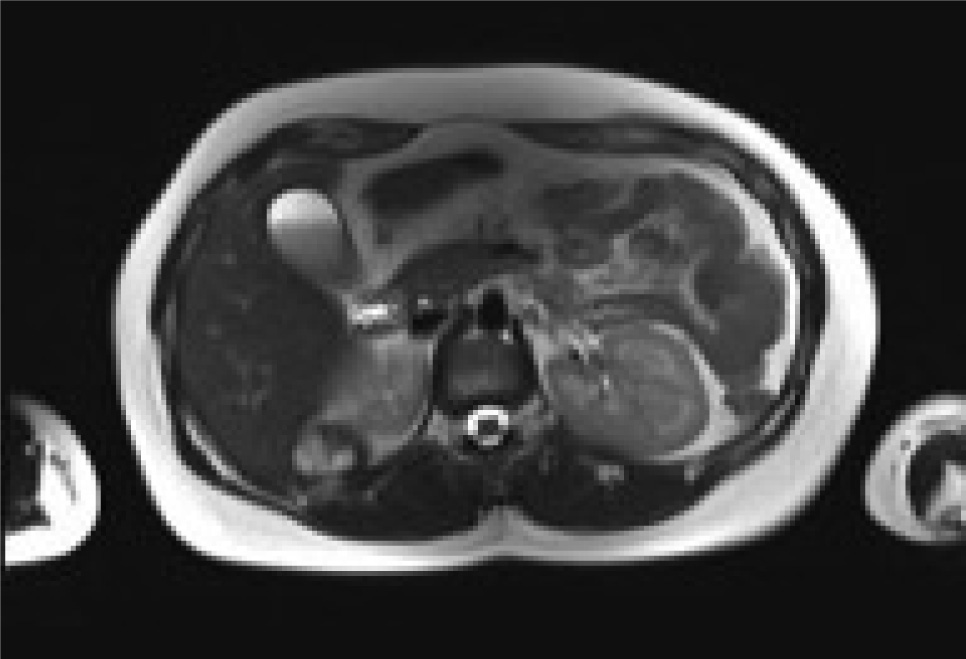

A 78-years old Moroccan woman was admitted to our department for a right flank pain without any other relevant symptoms or signs; she referred to only a light pain radiating to the epigastric region. The pain had started eight or ten months previously, she had no nausea or vomiting, she was afebrile and her vital signs were normal. She denied any contact with dogs or sheep and she had moved from Morocco to Italy in 2009. She was unemployed. Her physical examination was normal, without any significant signs or symptoms, which could suggest retroperitoneal abdominal masses. When she was a child she had the common infective diseases and at the moment of physical examination she had only an iron deficiency anemia. She underwent two Caesarean Births in 2009 and 2012. We performed routine laboratory exams on her, such as hemocromocitometric panel, major biochemical values and principal enzymes; there was no pathological alteration. She underwent ultrasound abdominal exam so we found a strange ovoidal hypoechoic formation in the right adrenal gland space; it was four centimetres in maximum diameter, and there were no signs of peripheral or central vascularization at Doppler’s exam; it was impossible to establish a sure diagnosis so we proposed a CT scan of the abdomen. The CT scan showed a solid mass of maximum diameter 5 cm, with a light peripheral vascularization and degenerative cystic areas; it had no clear linkage with either liver or with right adrenal gland. Therefore we decided to admit her to perform other imaging and laboratory exams; in fact we required an abdominal MRI which showed: “mass of 34 x 27 mm with a central cyst composed of a multilocular structure, there are signs of parietal vascularization and there aren’t signs of a clear dissection plane from kidney and liver”(image 1,2,3,4). Despite this we continued with a screening exam for HD such as indirect hemaglutination test and also hormonal exams both for adrenal cortex hormones and medullar catecholamines; all these exams were negative. We decided to perform a surgical approach to this mass, because we had to have a sure histological diagnosis of the mass; we gained the informed consent for surgical procedure. We set up the patient on the operating table in lateral left decubitus, we obtained a pneumoperitoneum with open technique and after an accurate exploration of abdominal cavity placed another three trocars to complete the procedure. We gained access to the retroperitoneal space with the same surgical steps of a laparoscopic adrenalectomy. There were significant adhesions between the unknown mass and the liver, kidney and adrenal gland. The mass was removed after a dissection through an unclear plane between liver and lesion. We extracted it into a laparoscopic bag from the access in right flank (image 5). The postoperative course was regular, without relevant complications. Unfortunately the definitive histological report was unclear. There was a significant rise in IG indirect hemagglutination one month after the surgical procedure (Indirect Haemoagglutination Assay was 1:600). Therefore we called a specialist for expert advice and finally we reached a conclusive diagnosis: Hydatid cyst localized in the retroperitoneal right adrenal gland space. Now the patient is in good health; even so, we have prescribed her a prophylactic drug treatment with albendazole.

Rm scan T1weighted axial image showing the adrenal mass